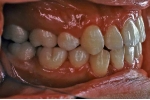

治療中